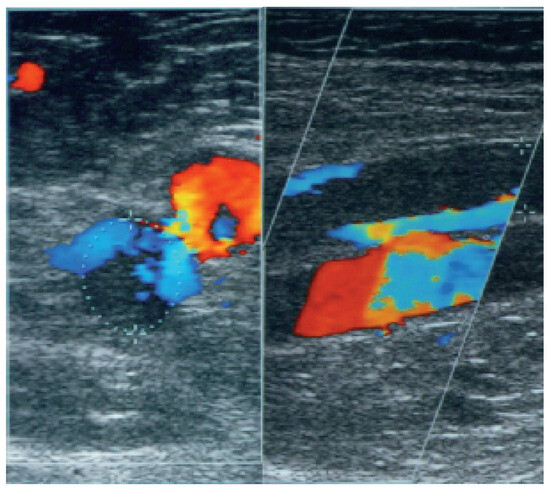

Fallbeschreibung. Ein 10jähriger Knabe wurde zur Abklärung eines Systolikums bei unauffälliger Anamnese und insbesondere uneingeschränkter körperlicher Belastbarkeit vorgestellt [...]